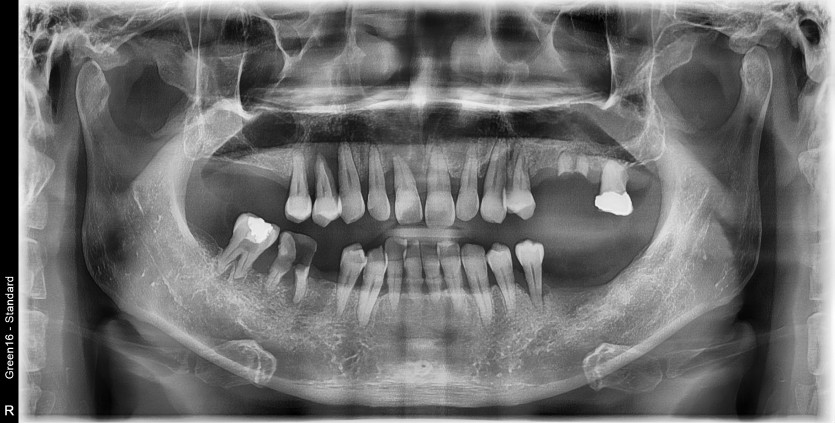

만 49세 전체 임플란트 증례

전체 임플란트 증례입니다.

14개의 임플란트로 완성하였습니다.